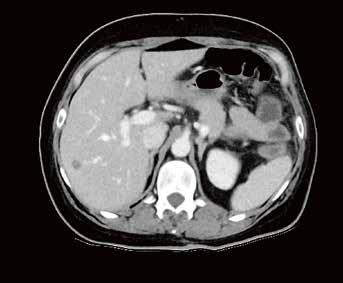

Fall 1:

Biphasische Abdomen-CT bei einer deutlich adipösen Patientin. Hier lässt sich sowohl Dosis sparen als auch die Qualität der Rekonstruktionen verbessern. Beispielsweise findet sich deutlich weniger Bildrauschen, insbesondere im Bereich der parenchymatösen

Fall 2:

Portalvenöse Abdomen-CT. Auch hier ist die Dosis am Aquilion Prime SP mit AiCE geringer, zudem auch hier geringeres Bildrauschen mit sehr guter Abgrenzbarkeit, beispielsweise von Leberläsionen.

Abb. 1 a: biphasische Abdomen-CT, Canon Aquilion Prime, Rekonstruktion: AIDR 3D; DLP 1003,6 mGy × cm / 18,1 mSv. Abb. 2 a: biphasische Abdomen-CT, Canon Aquilion Prime, Rekonstruktion: AIDR 3D; DLP 1003,6 mGy × cm / 18,1 mSv. Abb. 1 b: biphasische Abdomen-CT, Canon Aquilion Prime, Rekonstruktion: AiCE; DLP 716,5 mGy × cm / 12,9 mSv. Abb. 2 b: biphasische Abdomen-CT, Canon Aquilion Prime, Rekonstruktion: AiCE; DLP 716,5 mGy × cm / 12,9 mSv. Oberbauchorgane.